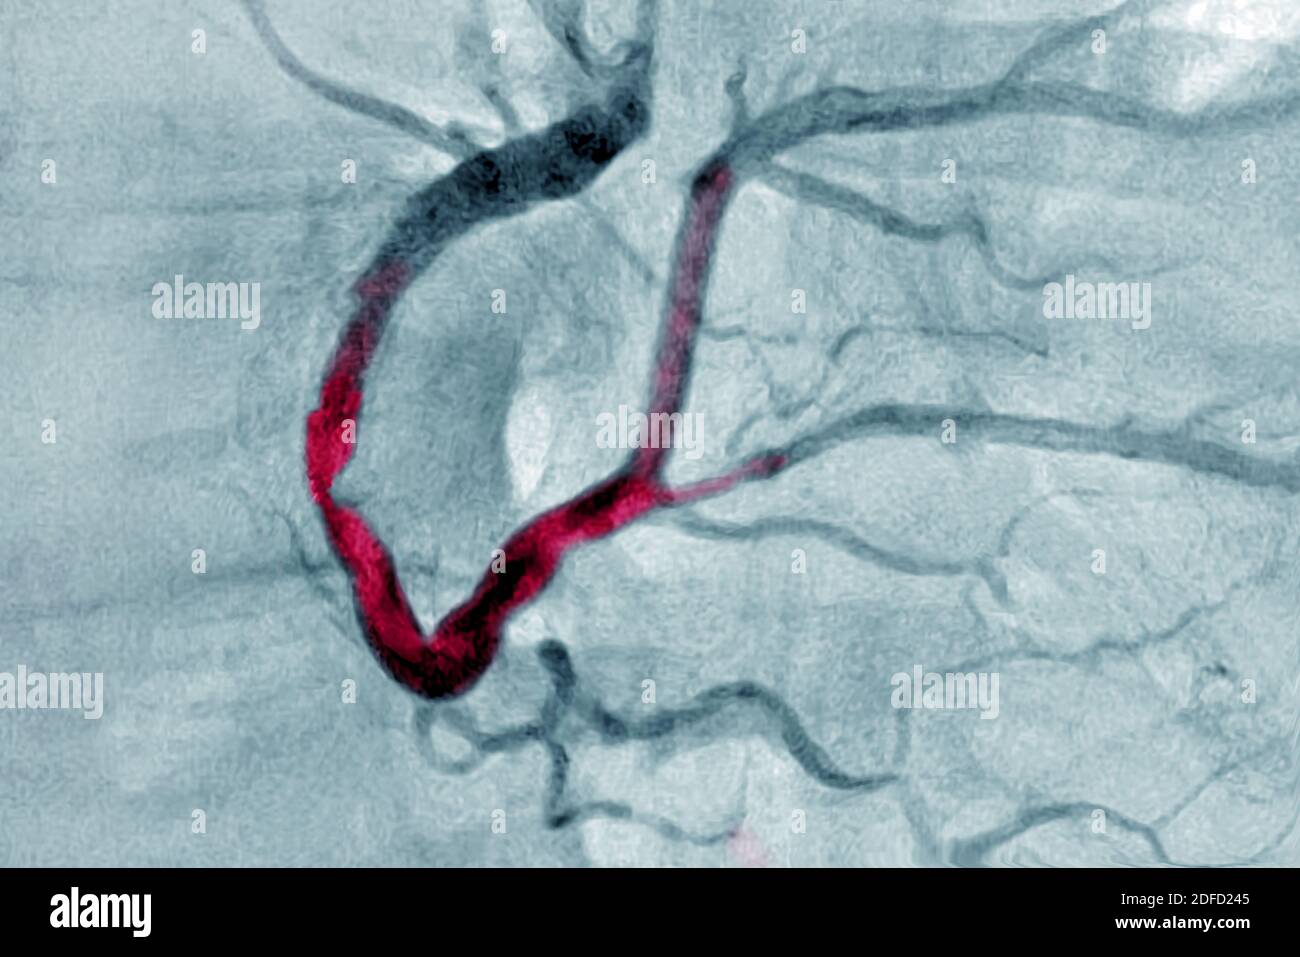

Myocardial infarction with a significant thrombus in the right coronary artery and extends into the left retro ventricular and the posterior intervent Stock Photohttps://www.alamy.com/image-license-details/?v=1https://www.alamy.com/myocardial-infarction-with-a-significant-thrombus-in-the-right-coronary-artery-and-extends-into-the-left-retro-ventricular-and-the-posterior-intervent-image388134997.html

Myocardial infarction with a significant thrombus in the right coronary artery and extends into the left retro ventricular and the posterior intervent Stock Photohttps://www.alamy.com/image-license-details/?v=1https://www.alamy.com/myocardial-infarction-with-a-significant-thrombus-in-the-right-coronary-artery-and-extends-into-the-left-retro-ventricular-and-the-posterior-intervent-image388134997.htmlRF2DFD245–Myocardial infarction with a significant thrombus in the right coronary artery and extends into the left retro ventricular and the posterior intervent